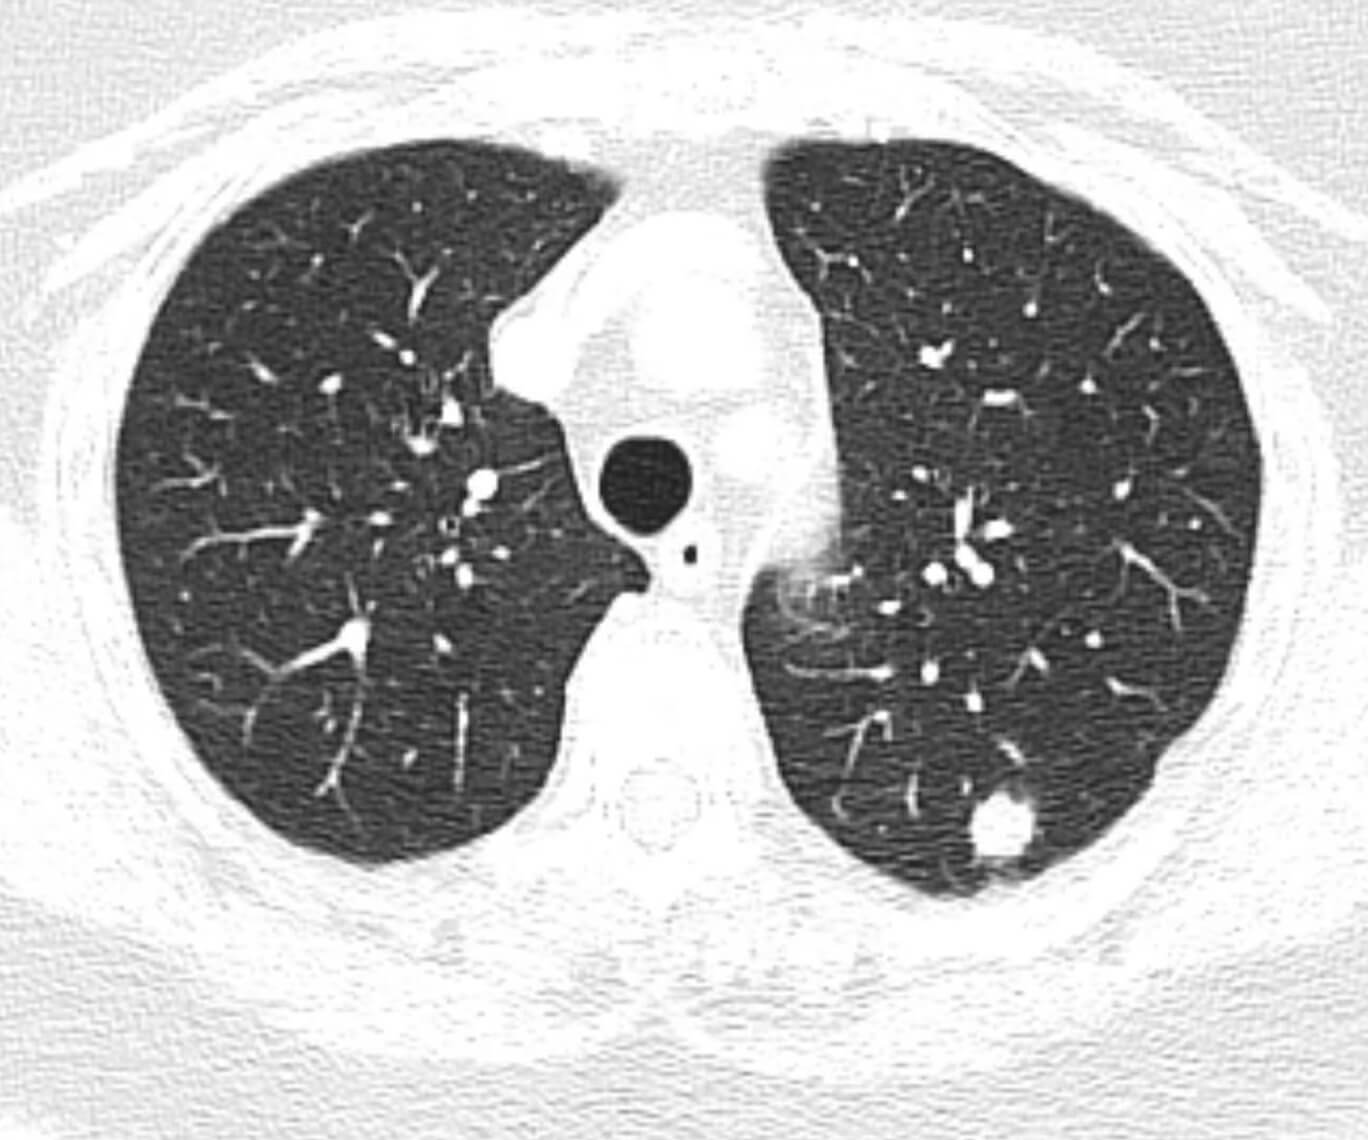

Рис. 2 — КТ органов грудной клетки с внутривенным контрастированием. В нижней доле левого легкого визуализируется солитарный очаг. С учетом анамнеза и рентгенологической картины, наиболее соответствует вторичному поражению.